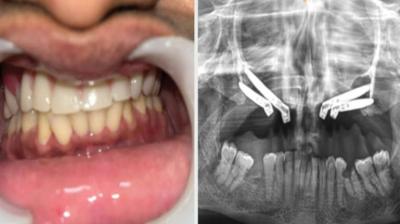

24 वर्षीय युवती के चेहरे पर लौटी मुस्कान और आत्मविश्वास

6 Sep, 2025 10:00 PM IST | INDIANSTATENEWS.COM

एम्म में जटिल सर्जरी को सफलतापूर्वक अंजाम दिया है। इस सर्जरी में ट्यूमर के कारण काटे गए निचले जबड़े को पैर की हड्डी से दोबारा बनाया गया और उसमें 13...